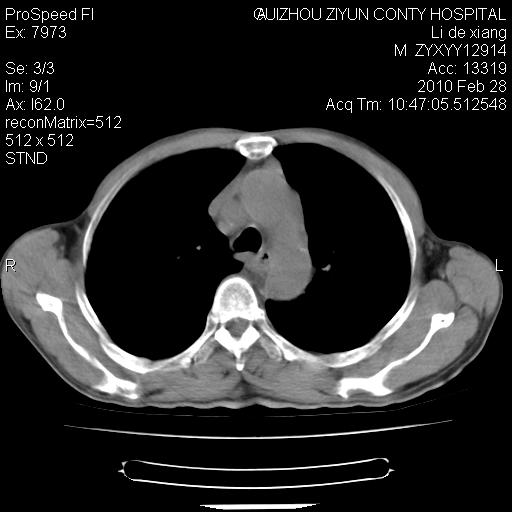

标题: CT24776:男 71Y 咳嗽咳痰胸痛两月,伴声音嘶哑。 [打印本页]

标题: CT24776:男 71Y 咳嗽咳痰胸痛两月,伴声音嘶哑。

左侧中央型肺癌伴左肺上叶阻塞性肺炎及节段性不张可能性大,建议纤支镜检查!

左侧中央型肺癌伴左肺上叶阻塞性肺炎及节段性不张可能性大,建议纤支镜检查!纵隔淋巴结转移.

左侧中央型肺癌伴左肺上叶阻塞性肺炎及纵隔淋巴结转移。

左肺门部肿块,伴左上肺斑块影,周边模糊,支持左肺中央型肺癌伴节段性不张及阻塞性肺炎,结合支气管镜检查。

左上叶支气管狭窄,阻塞性病变,肺门肿块,纵隔及肺门淋巴结增大,中央性肺癌

左肺中央型肺癌并阻塞性改变、纵膈 淋巴结转移

左侧中央型肺癌伴左肺上叶阻塞性肺炎及纵隔淋巴结转移